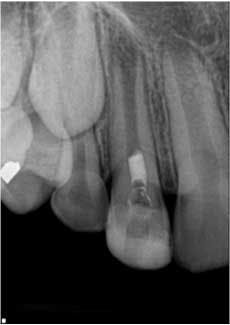

At the second visit, the tooth was anesthetized with an anesthetic that had no vasoconstrictors (to increase the likelihood of getting a blood clot in the tooth, Petrino et al., 2010), isolated, and accessed. The canals were irrigated with 20 ml of 5.25% NaOCl. After irrigation, the canal system was dried and a small, stainless steel hand file was used to lacerate the periradicular tissue to induce bleeding into the canal system. Once there was evidence of blood flow back into the canal, Collaplug (Zimmer Dental, Carlsbad, Calif.) was placed into the canal system to help create a barrier at the coronal portion of the canal. After formation of the blood clot, white MTA was condensed on top of the Collaplug to seal the canal system. The tooth was temporized, and the patient was instructed to return to his general dentist for restoration of the access (Fig. 2).Fig. 2: Tooth No. 7 after second visit showing placement of the MTA barrier.The patient was placed on recall and returned approximately eight months following treatment. The patient and parent reported that the tooth was not restored, but had been asymptomatic. Clinically, the tooth was asymptomatic, and radiographs showed signs of resolution of the apical radiolucency, increased thickness of the root walls, and apical closure. The patient was encouraged to have the access restoration restored. (Fig. 3) The patient returned at 15 months for his next recall examination, and the tooth had a permanent restoration. Clinically, the tooth was asymptomatic, and radiographs showed evidence of apical bone healing, increased thickness of the root walls, and apical closure. (Fig. 4)

Fig. 3: Eight-month recall. Note the resolution of the apical periodontitis and continued development of the root walls and apical closure.